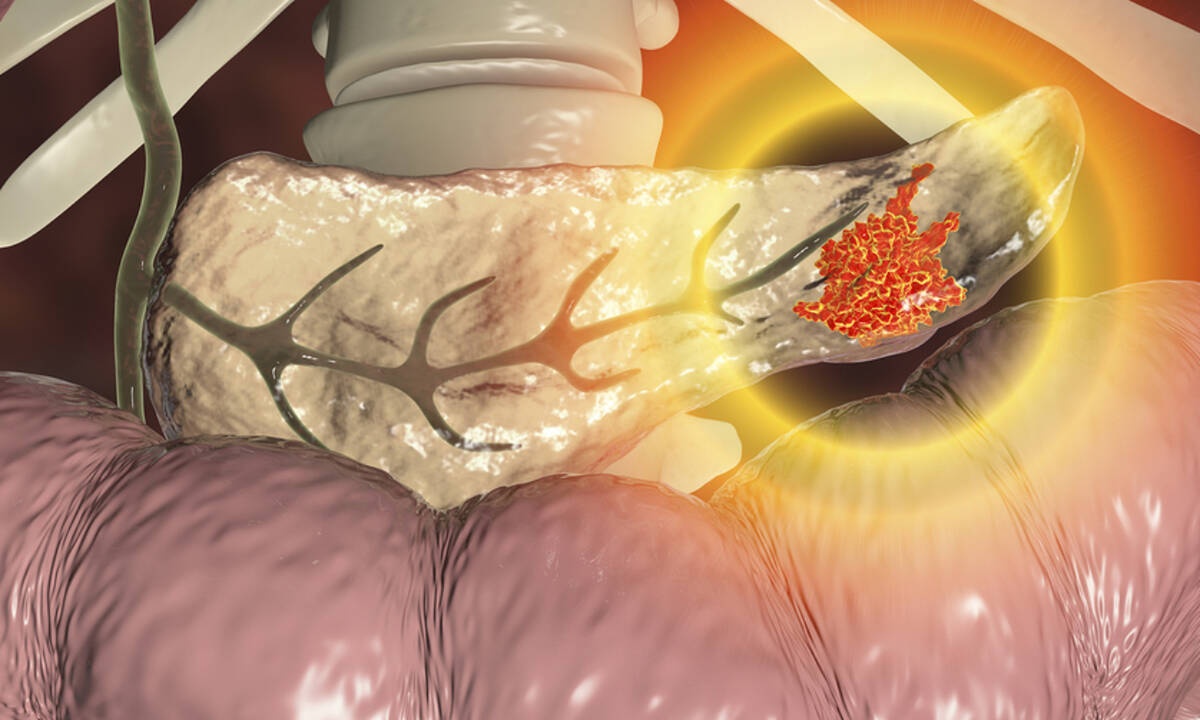

Πάγκρεας: Τα ανησυχητικά σημάδια που πρέπει να γνωρίζετε (εικόνες)

Το πάγκρεας είναι ένα όργανο που βρίσκεται κεντρικά στο πάνω μέρος της κοιλιάς και πίσω από το στομάχι και τα έντερα.

Δείτε στις εικόνες που ακολουθούν τα συμπτώματα του καρκίνου του παγκρέατος, καθώς η έγκαιρη διάγνωση μπορεί πραγματικά να αυξήσει την πιθανότητα επιβίωσης από τον καρκίνο του παγκρέατος: